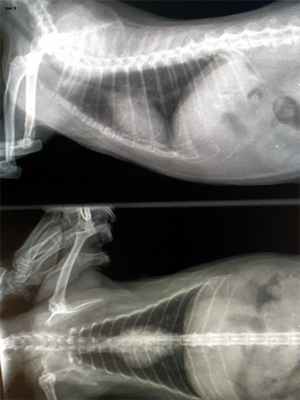

С целью контроля течения аспирационной пневмонии требуется повторение рентген-диагностики. Контрольный рентгеновский снимок был сделан через 2.5 месяца (рис 3).

По данным рентгена и отсутствия клинических симптомов кот был клинически здоров.